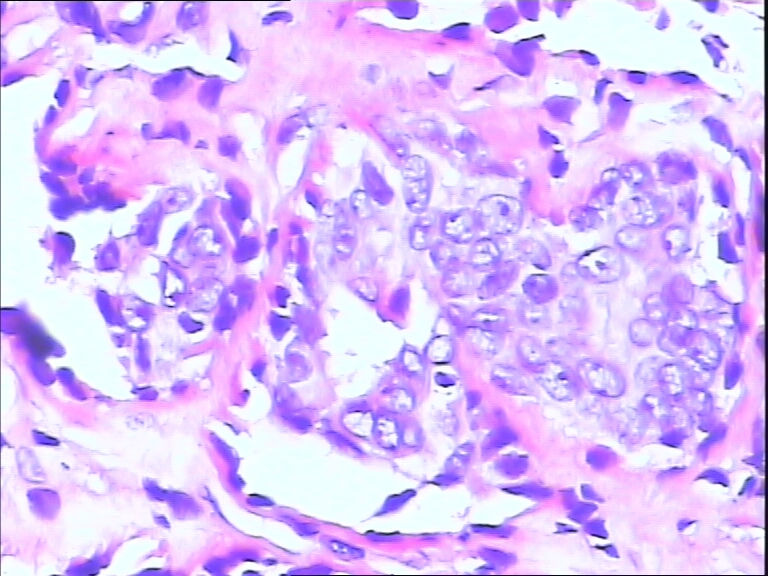

42y

左乳头有3mm结节

灰白不整形组织一块:0.7*0.5*0.4

导管内乳头状肿瘤